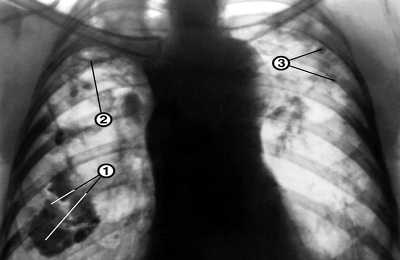

image

Инфильтративная форма

Это наиболее распространенная форма туберкулеза, которая встречается более чем в 60 % случаев. Она характеризуется распространенным некрозом (гибелью) ткани легкого. В зависимости от того, что показывает флюорография легких, выделяют несколько подтипов инфильтративного туберкулеза:

• круглый инфильтрат — затемнение овальной или округлой формы в верхних отделах легких, чаще всего под ключицей;

• облаковидный инфильтрат — тень однородной структуры с неровными границами;

• краевой инфильтрат — тень имеет форму треугольника, вершина которого направлена к корню легкого;

• дольковый инфильтрат — представляет собой группу слившихся очагов различной плотности;

• лобит — тень больших размеров, охватывающая целую долю легкого, имеет неоднородную структуру.